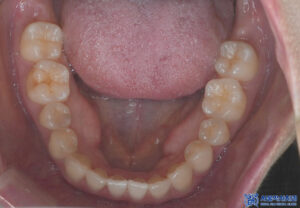

이렇게 계획된 치료가

모두 마무리되었습니다.

마무리 후 사진입니다.

어금니 크라운도

심미적으로나 기능적으로나

자연스럽다며 좋다고

말씀해 주셨습니다.